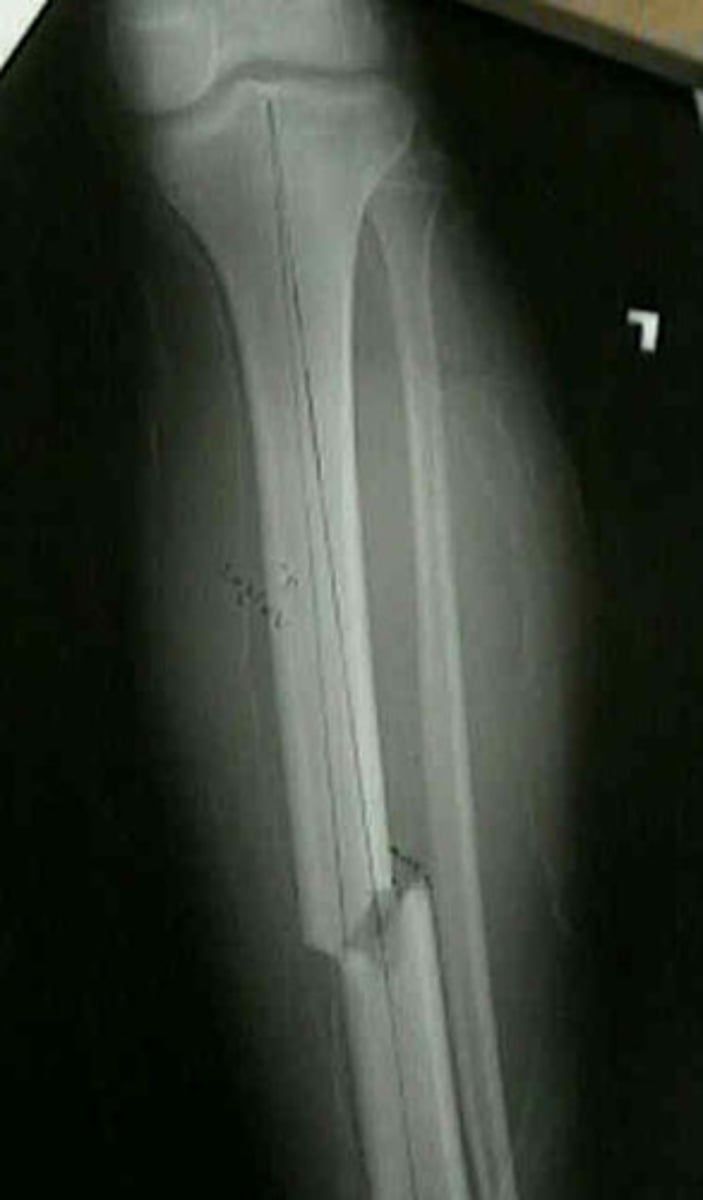

Comminuted fracture

fracture in which the bone is splintered or crushed